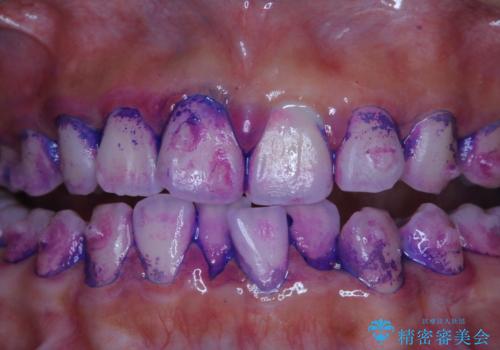

しかし、プラークは歯の色と似ているため、見ただけでは付着しているかどうかがハッキリとは分かりません。

染め出し液を使ってプラークを染め出すことにより、普段の歯みがきで磨き残している場所を目で確かめることができます。

日々の歯磨きを上達するには、まずどこが磨けていないか認識することが大切です。